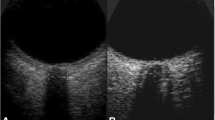

Transorbital Ultrasound Measurement

A Canon Aplio i800 (Japan) ultrasound device with an 18-MHz linear array transducer was used. Following the “as low as reasonably achievable” principle [15], the mechanical index and thermal index were adjusted to the requirements of orbital sonography. The patients were examined in a supine position with their heads elevated to 20–30°. The probe was gently placed on the closed left and right upper eyelids with coupling gel and adjusted to a suitable angle to show clear images with hyperechoic striped bands. Images in the transverse and sagittal sections of each eye were stored for measurement, and then we measured ONSD-related parameters at a depth of 3 mm behind the retina (Fig. 1). The ONSD-related parameters were the OND (measured as the distance inside the pia mater), ONSDI (measured as the distance between the external borders of the hypoechogenic dura mater), ONSDE (measured as the distance between the hyperechogenic subarachnoid diameter), ONSDI-OND, and ONSDI/ETD. All ONSD-related parameters were measured twice in the transverse and sagittal orientations for each eye, and then the final value was derived from the average of the eight values.

Image of optic nerve sheath with hyperechoic striped bands (left). The distance between the two yellow lines denotes ONSDI, the distance between the two blue line denotes ONSDE, and the distance between the two red line denotes OND (right). OND optic nerve diameter, ONSDE optic nerve sheath diameter excluding the dura mater, ONSDI optic nerve sheath diameter including the dura mater (Color figure online)